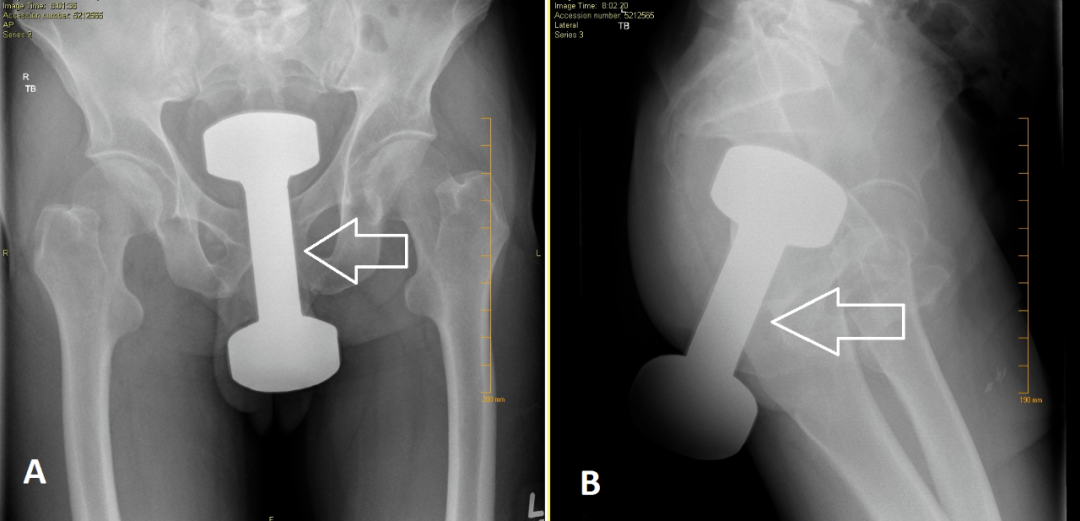

又到了大家最喜歡的看圖猜異物環節

請將答案按順序寫在評論區